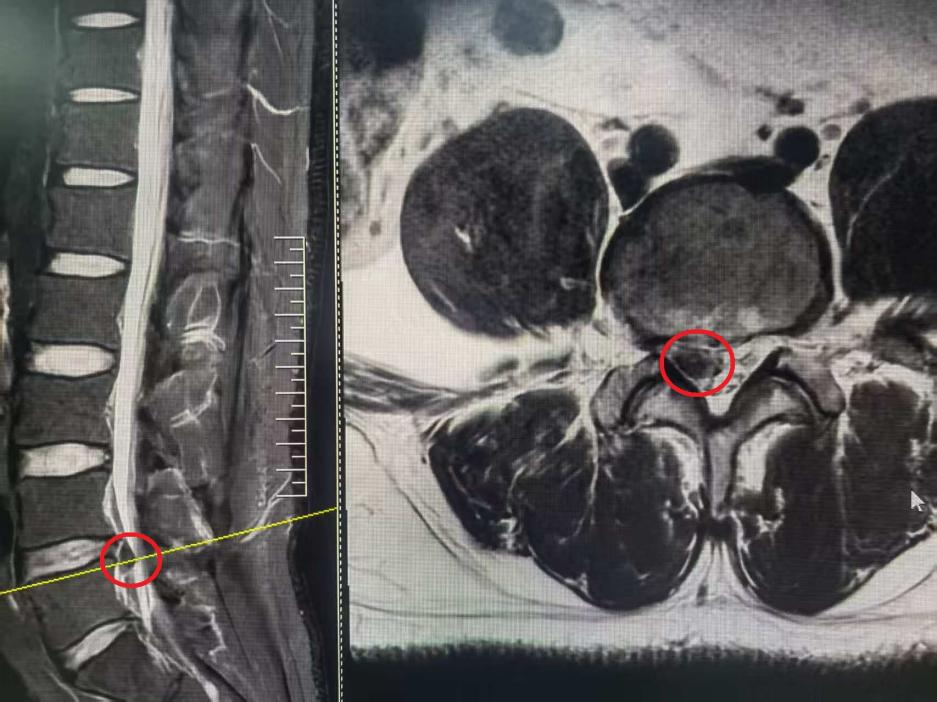

3个月前,王先生出现腰痛伴右下肢麻痛,活动受限,以下肢症状为主,经过保守治疗后症状不缓解,他慕名来到河南省直第三人民院脊柱微创外科,寻求微创治疗。

患者入院检查之后发现,病因是腰椎间盘脱出,压迫神经,导致右腿的疼痛麻木

入院检查腰椎磁共振

根据检查结果及患者症状和诉求,医生选择了椎间孔镜微创手术